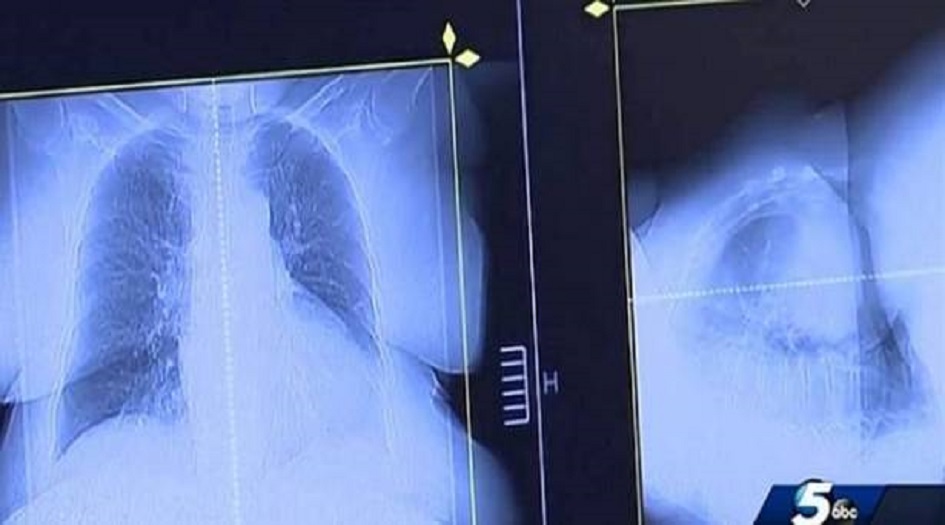

في كانون الثاني 2017، كان جو تيبنس واثقاً من موته قريباً بسرطان الرئة لكن طبيباً بيطرياً اقترح عليه الاستعانة بعقار “فينبيندازول”، وهو مركب مضاد للديدان يستخدم لعلاج الديدان الخطافية والمستديرة وغيرها من الطفيليات المعوية لدى الحيوانات، خاصةً الكلاب.

وفي السنوات الأخيرة، أظهرت الدراسات أن العقاقير المضادة للديدان قد يكون لها خصائص مضادة للسرطان، ورغم أنه لم تثبت فعالية هذا العلاج، إلا أن تيبس لم يكن لديه ما يخسره، بعدما توقع الأطباء وفاته في غضون 3 أشهر، فقرر العلاج بهذا العقار.

وتناول حبوب علاج الكلاب، لكنه لم يخبر طبيبه بذلك، وأظهرت فحوصات خضع لها في أيلول 2017 تحسناً كبيراً في حالته.

وفي كانون الثاني 2018، خضع تيبس لمسح نهائي لكشف تطور مرضه، وكانت المفاجأة انه شفي تماماً من السرطان.